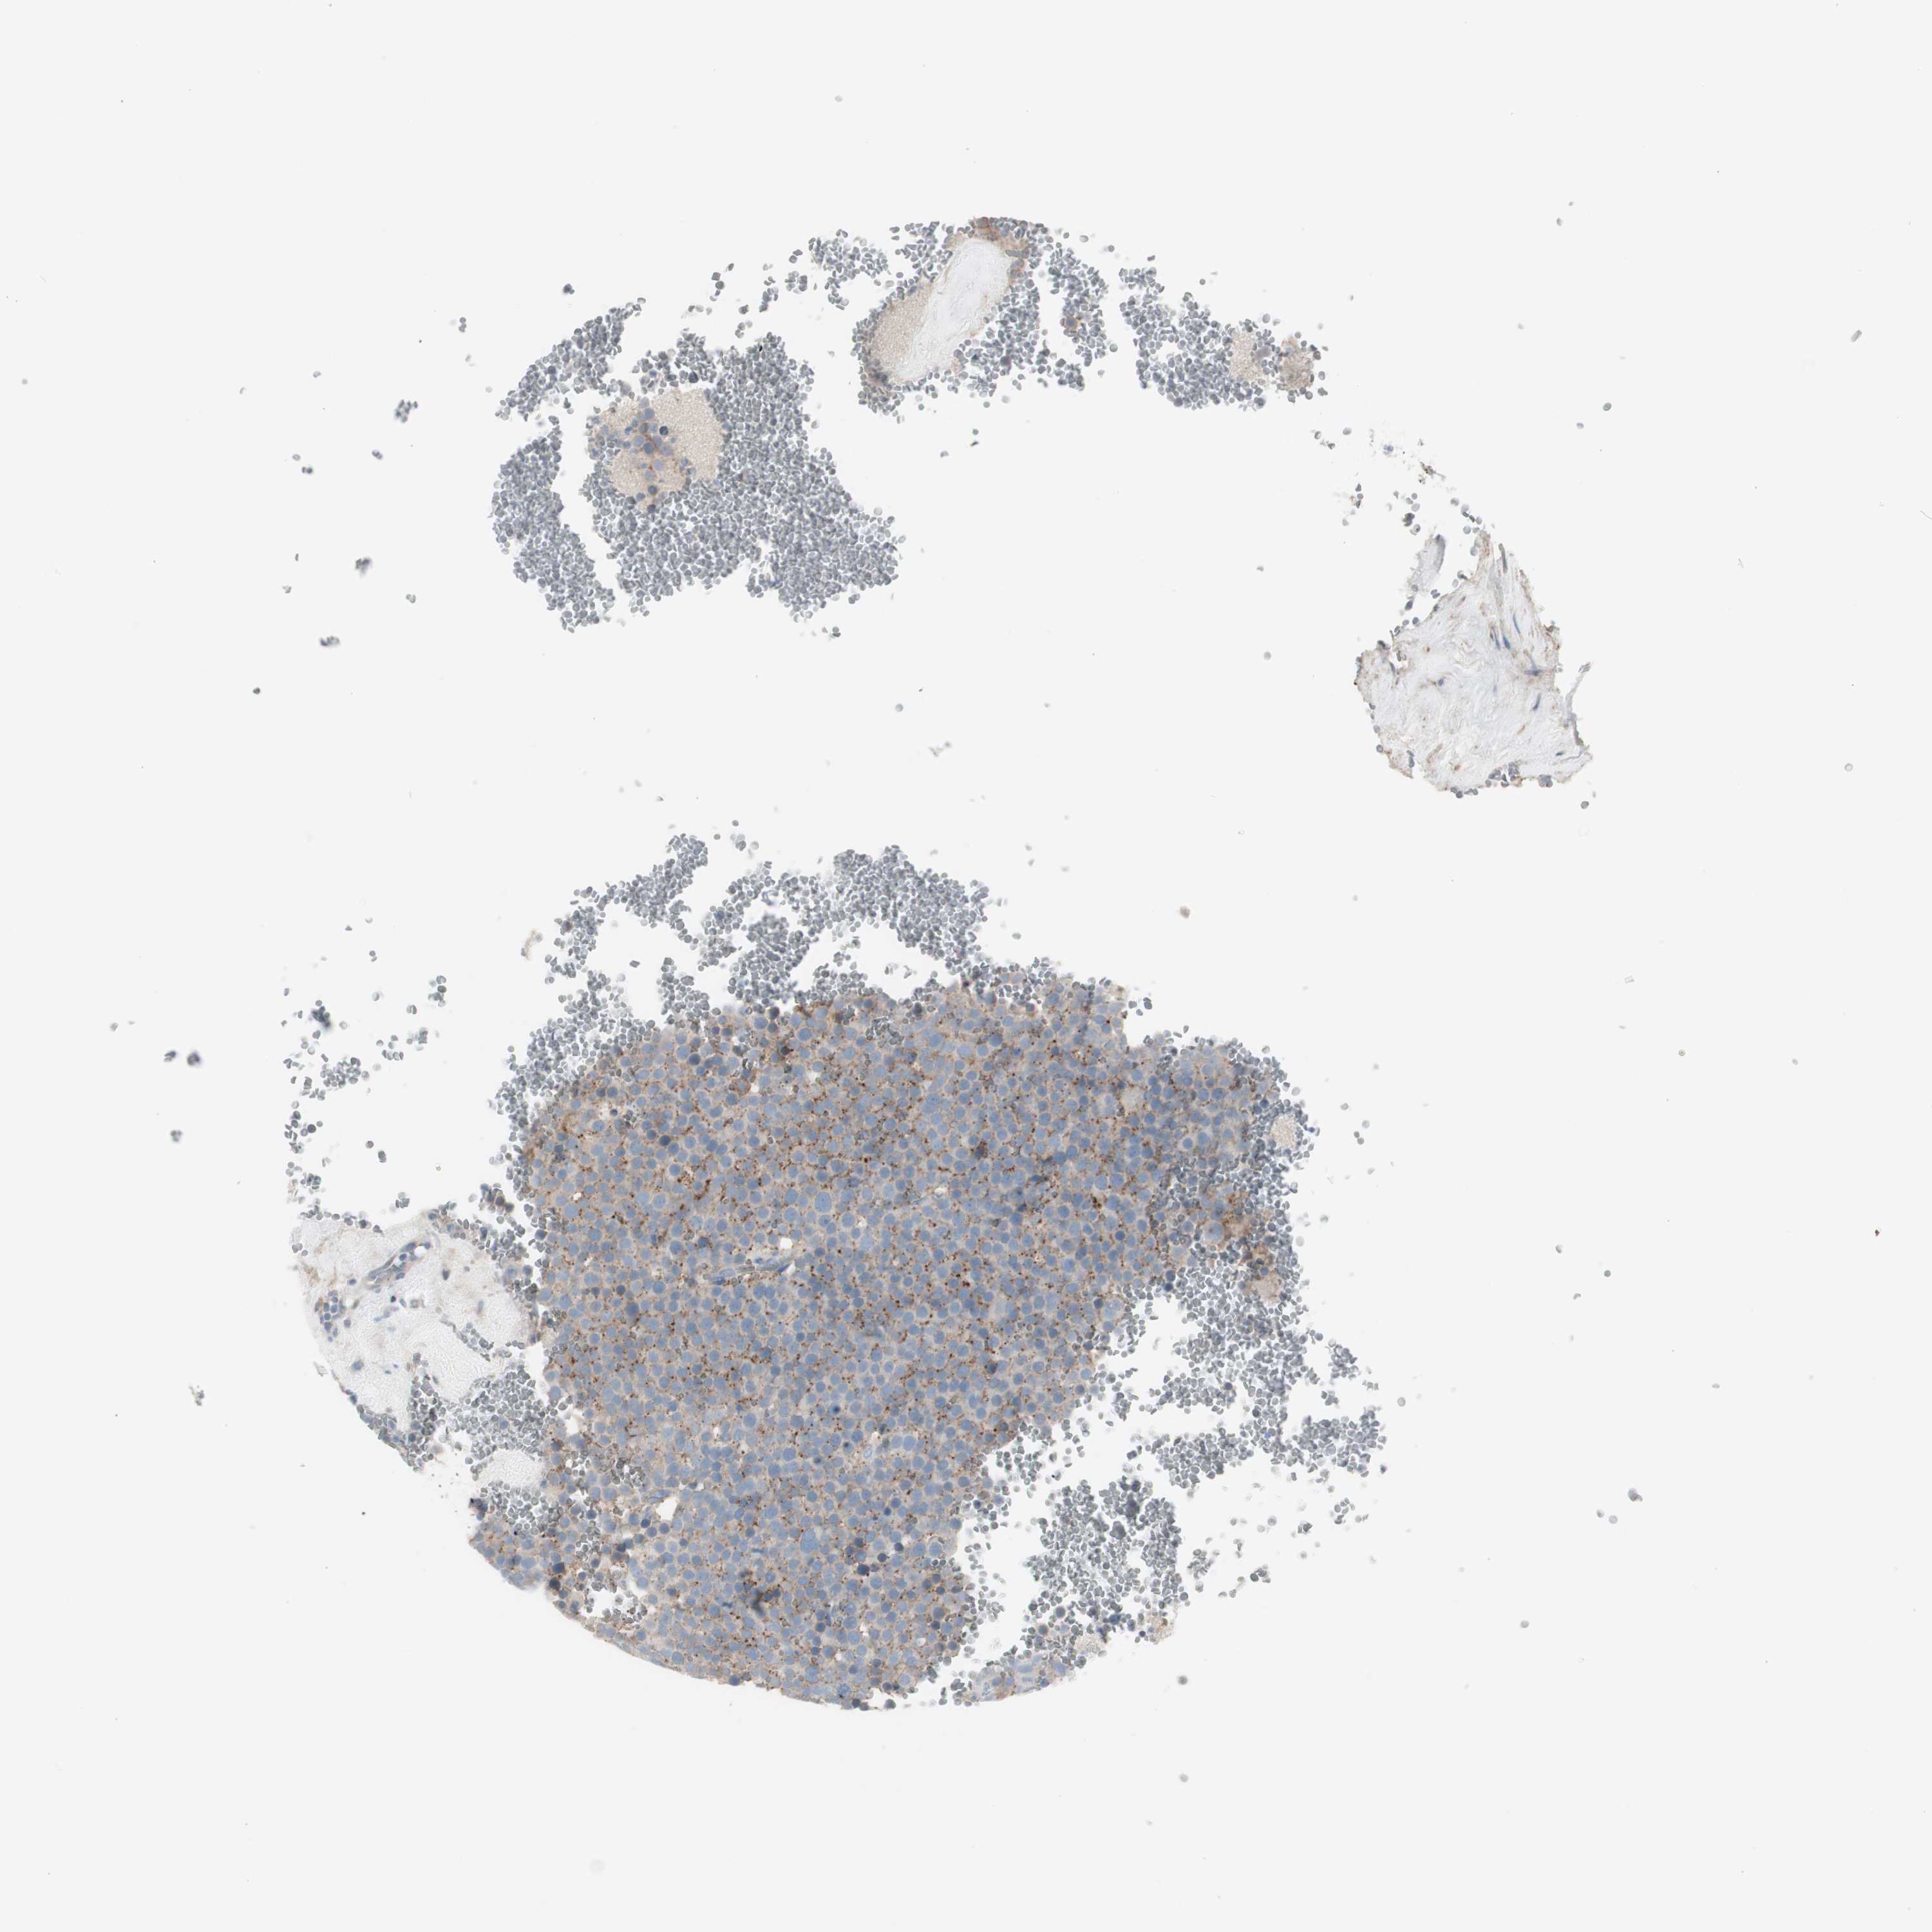

TESTIS CANCER - Protein expressioni

A mouse-over function shows sample information and annotation data. Click on an image to view it in a full screen mode. Samples can be filtered based on level of antibody staining by selecting one or several of the following categories: high, medium, low and not detected. The assay and annotation is described here.

Note that samples used for immunohistochemistry by the Human Protein Atlas do not correspond to samples in the TCGA dataset.

Antibody stainingi

Antibody staining in the annotated cell types in the current human tissue is reported as not detected, low, medium, or high, based on conventional immunohistochemistry profiling in selected tissues. This score is based on the combination of the staining intensity and fraction of stained cells.

Each image is clickable and will lead to virtual microscopy that enables deeper exploration of all samples and also displays staining intensity scores, fraction scores and subcellular localization as well as patient and tissue information for each sample.

Antibody HPA008213

Antibody HPA008621

Staining

High

Medium

Low

Not detected

Intensity

Strong

Moderate

Weak

Negative

Quantity

>75%

75%-25%

<25%

None

Location

Nuclear

Cytoplasmic/membranous

Cytoplasmic/membranous,nuclear

Carcinoma, Embryonal, NOS

Seminoma, NOS